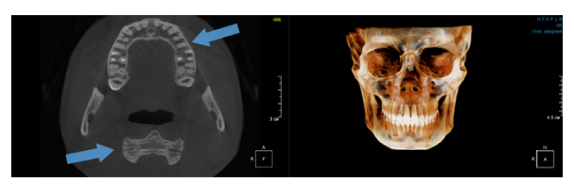

Когда мы отправляем пациента на проведение рентгенологического исследования, то подвергаем его определенному риску. Именно это нужно осознавать, так как в радиологии нет минимально безопасной дозы, поэтому любое назначение должно быть обоснованным. В связи с этим поле обзора является достаточно принципиальным параметром. Если вы врач-терапевт, занимающийся эндодонтией или ортопед, который решил оценить состояние зубов перед протезированием, то вы должны понимать, что проведение исследования с полем обзора 10x10 см будет гораздо информативнее нежели большие снимки (18x16 см и выше). В первую очередь это связано с размером вокселя, о нём я напишу чуть ниже, а второе это то, что вам придется увеличивать изображение по каждому корневому каналу, и от этого вы будете терять в качестве снимка (рис. 1). И ситуация наоборот, если вы ортодонт, то чтобы использовать весь диагностический потенциал, а также возможность загрузить данные для расчёта 3D цефалометрии, то вам нужны снимки, захватывающие весь лицевой отдел черепа. Таким образом, дентальный томограф должен обладать возможностью проведения исследований с разным FOV, обеспечивая нужды всех специалистов. Если ваша клиника базируется на терапевтическом, хирургическом и ортопедическом приёме, то на мой взгляд, можно рассмотреть дентальные томографы с полем обзора 10x10 см или 16x10 см. Последний больше актуален для тех, кто работает с ВНЧС, так как антропометрически в 16 см даже у брахицефалов сустав должен попадать.  Если в клинике есть ортодонтическое направление, функциональная стоматология, ЛОР-практика или ЧЛХ, то, безусловно, вышепредставленные снимки не будут отражать всех данных, которые необходимы для диагностики и планирования лечения. Здесь лучше рассмотреть конусно-лучевые компьютерные томографы с зоной сканирования 18x16 или 20x20 см. Особо стоит отметить понятие «сшивки». Есть дентальные томографы, которые делают один цельный снимок размерами, которые описаны выше, а есть аппараты, которым нужно провести две экспозиции и сшить изображения вместе, чтобы получился необходимый объём исследования. Как правило, вторые томографы чуть дешевле, но всё зависит от того, насколько вам нужна максимальная точность исследования. Если при сшивке челюсти и зубы, как правило, совмещаются практически идеально, то на уровне позвоночного столба происходит наслоение тканей и от него уже не избавиться (рис. 2). Второй отрицательный момент – это износ оборудования, логично, что он будет быстрее, так что экономия средств — это ещё спорный вопрос.

Рис. 2. Левый снимок представлен исследованием 20x20 см единым изображением. Стрелками показаны чёткость канально-корневой системы зуба, а также позвоночника. Правый снимок представлен исследованием 16x15 см с функцией сшивки. Стрелками обозначены чёткость зуба, но двойной контур позвоночника.